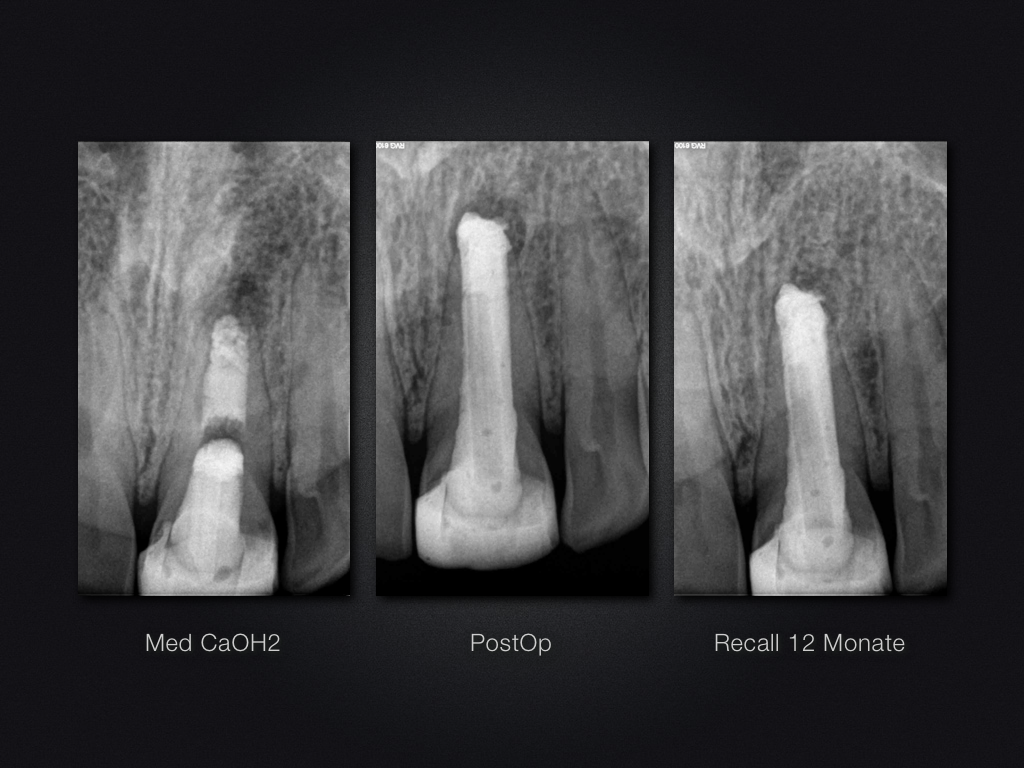

21D.007

Ofenrohr-das Recall